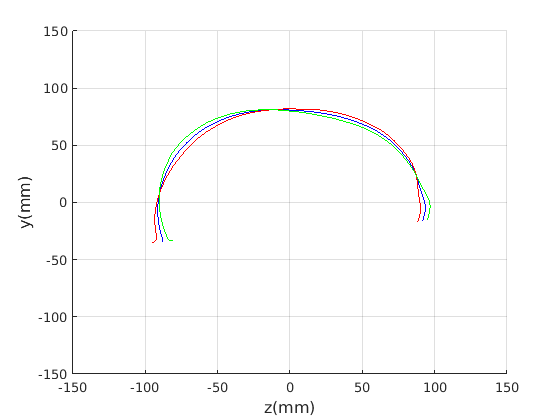

To emphasise the form/shape variation for each of these cases, the mean shape and shapes at mean for the four most significant modes of shape variation are plotted in Fig. 19 and Fig. 20. In this case, ECN normalisation is used.

For the craniofacial sagittal profile model, when not scale-normalised (Fig. 19, left column), the following four dominant shape modes are observed:

-

Cranial height, calvarium convexity and facial angle constitute the main correlated shape variations captured im mode 1, with small cranial heights being correlated with a depression in the region of the bregma. There appears to be a waisting variation where the calvarium alternates between convex (high cranial height) and concave (low cranial height) configurations. Cranial height and ’waisting’ are also strongly correlated with the angle of the face relative to the line between the cranial ellipse centre and nasion.

-

2.

The overall size of the head varies : surprisingly this appears to be almost uncorrelated with craniofacial profile shape. This was only found in the ECN method of pose normalisation.

-

3.

The length of the face varies - there is variation in the ratio of face and cranium size.

-

4.

Variation in the chin size. A smaller chin appears to be correlated with a more prominent forehead.

The fact that the facial orientation appears to rotate initially led us to suspect a flawed pose normalisation procedure. However, the point about ECN normalisation is that it focuses on aligning the crania rather than faces, using its centre and the nasion, and the face has to follow that normalisation. Thus these results should be interpreted with a fixed cranial ellipse centre and fixed ellipse centre to nasion angle in mind.

To provide a comparsion with ECN, the form/shape variation modes extracted from a GPA-based alignment are given in Fig. 21 for full head and Fig. 21 for cranium only.